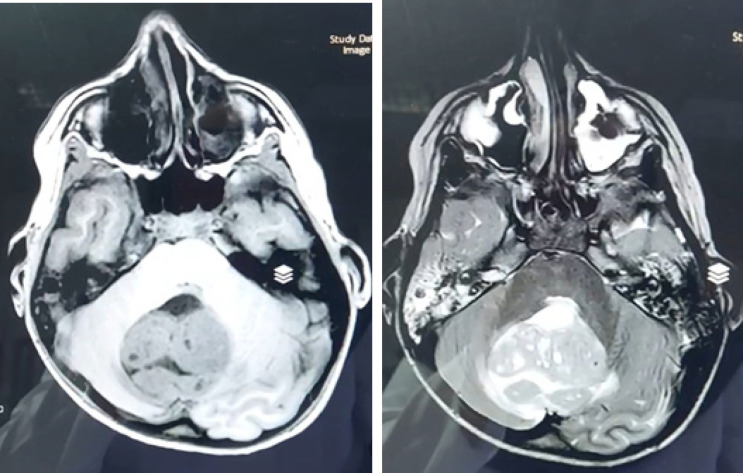

Materials & methods: This retrospective cross-sectional study was conducted on all pediatric patients with posterior fossa tumors admitted to teaching hospitals affiliated with Isfahan University of Medical Sciences from 2017 to 2022. Forty-three patients with posterior fossa tumors were identified, and seven patients were excluded due to diagnoses other than medulloblastoma or ependymoma. Tumor morphology on MRI, tumor density on CT scan, and apparent diffusion coefficient (ADC) values were assessed to differentiate medulloblastoma from ependymoma.

Results: Histopathologic diagnosis was medulloblastoma in 21 patients (60%) and ependymoma in 14 patients (40%). Mean ADC values in medulloblastoma and ependymoma cases were 0.67±0.19 (range= 0.50-1.25) and 1.22±0.29 (range=0.67-1.72), showing a significant statistical difference between the two groups (p-value=0.000). The ADC cut-off point of 0.9825 was associated with 90% sensitivity and 92.9% specificity for differentiation of ependymoma from medulloblastoma.

Conclusion: While tumor morphology on MRI and other studied parameters are unreliable for differentiating medulloblastoma and ependymoma, ADC values may provide a potential diagnostic tool. Further studies are needed to confirm the utility of DWI and other advanced MRI techniques in differentiating these tumors.